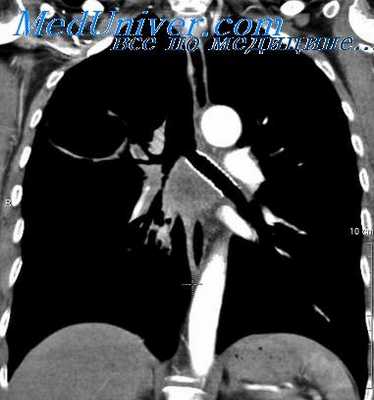

Двусторонние огнестрельные ранения грудной клетки с повреждением средостения обычно заканчиваются летально и только в очень редких случаях при благоприятных обстоятельствах (отсутствие травмы крупных сосудов и органов) могут протекать сравнительно легко.

Мы наблюдали 7 раненых, у которых проекция раневого канала отчетливо показывала двустороннее повреждение грудной клетки и средостения. Пневмоторакс у всех этих раненых, за исключением одного, был двусторонним, небольшим, закрытым. У 5 из них при рентгеноскопии был выявлен двусторонний незначительный гемоторакс, потребовавший пункции плевральных полостей.

Симптомы двусторонней травмы грудной клетки у этих раненых не отличались от обычных односторонних ранений и лечебные мероприятия были обычными: пункция плевральных полостей, ваго-симпатическая двусторонняя блокада, переливание крови, рассечение раны мягких тканей.

Только у одного раненого (23 лет) сильное кровотечение в левую плевральную полость и нарастающие симптомы гемоторакса и сдавления органов средостения заставили произвести левостороннюю торакотомию с резекцией IV ребра. Во время операции обнаружен почти полный разрыв внутригрудного отдела левой подключичной артерии. Последняя была перевязана выше и ниже места ранения. Смерть наступила на 5-е сутки от двусторонней пневмонии.

На аутопсии обнаружено двустороннее ранение обоих легких, небольшой двусторонний гемопневмоторакс, двусторонняя сливная бронхопневмония. В данном случае смерть последовала в результате пневмонии, осложнившей тяжелое двустороннее ранение грудной клетки.